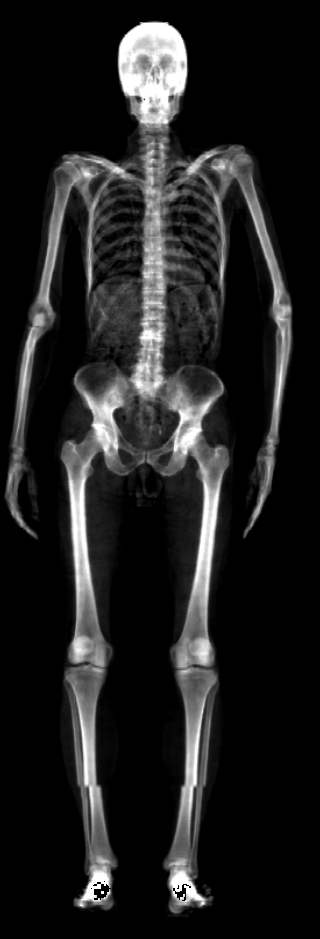

The key problem, however, is obtaining training data that simultaneously gives the inside and outside of the body in 3D. Most imaging technologies that simultaneously capture the inside and outside of the body use ionizing radiation, which is harmful to humans; e.g. Computed Tomography (CT) and X-rays. This means that such data is extremely limited, preventing learning-based methods. Our insight is to use dual-energy X-ray absorptiometry (DXA) data. DXA scans use low-dose X-rays to measure bone mineral density and body fat composition. The radiation level is so low that it is certified to be used on healthy patients for clinical studies, such as the UK Biobank [36]. In a DXA scan, two images are computed by combining two different energy levels: a soft-tissue image and a bone image (Fig. 2). In the silhouette of the body can clearly be seen, whereas reveals the structure and shape of the bones.

From the input images (, ), we compute the corresponding skin and skeleton segmentation masks (, ). For the skin mask , we threshold . As some small artifacts remain, mainly due to pixels in the lungs with low intensity values, we detect the closed contours on the image and fill in small areas. In Fig. 2 we show pairs of input and the obtained mask .